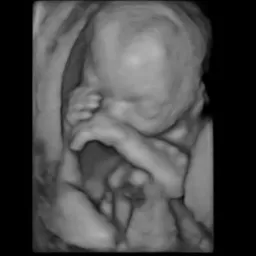

1. Upload your 3D ultrasound

Upload your 3D ultrasound to our secure platform

Upload your 3D ultrasound scan

Original